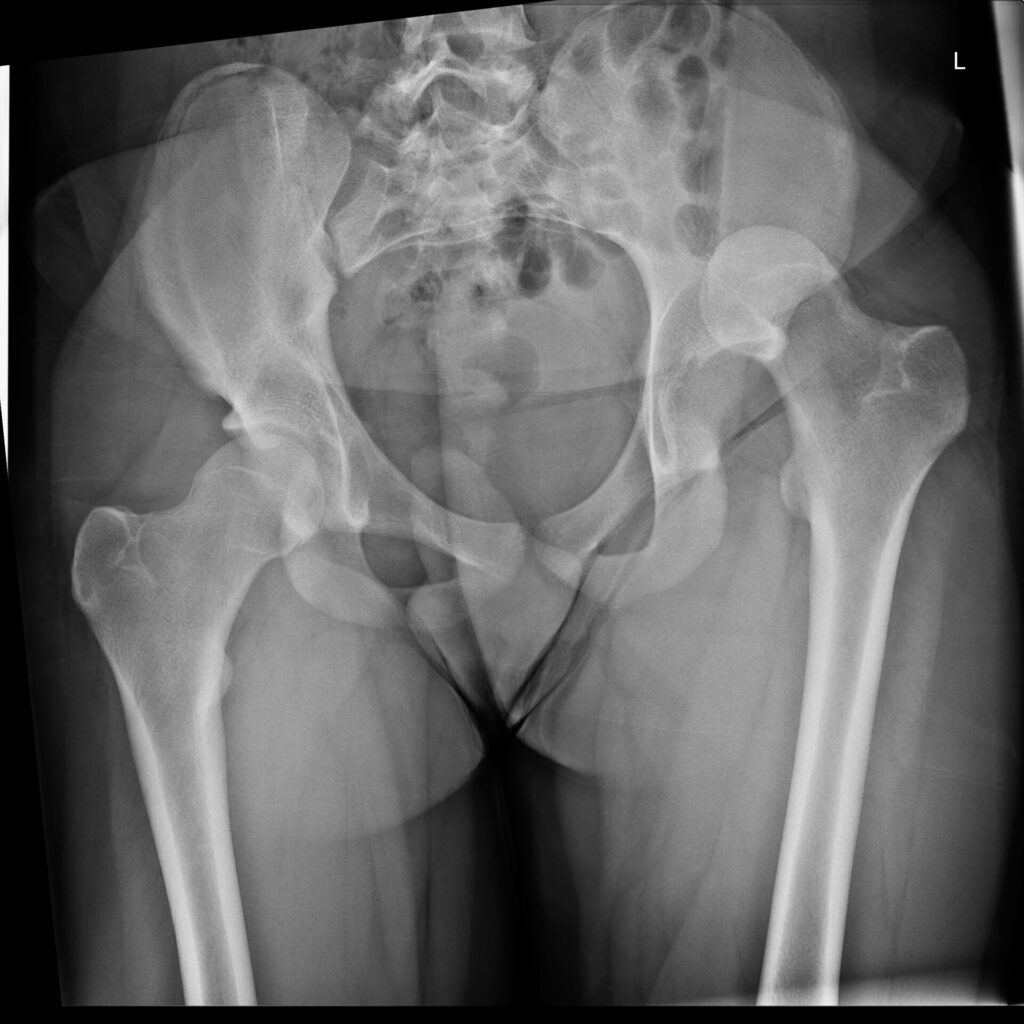

Reale Klinikbilder statt Demo-Grafiken.

Die spezialisierte Lernplattform für Projektionsradiographie. Im Mitgliederbereich steht eine stetig wachsende Fallsammlung mit realen Röntgenbildern zur Verfügung — systematisch aufgebaut, mit strukturierter Befundung, Befundcheck und klinisch relevanten Zusatzhinweisen.